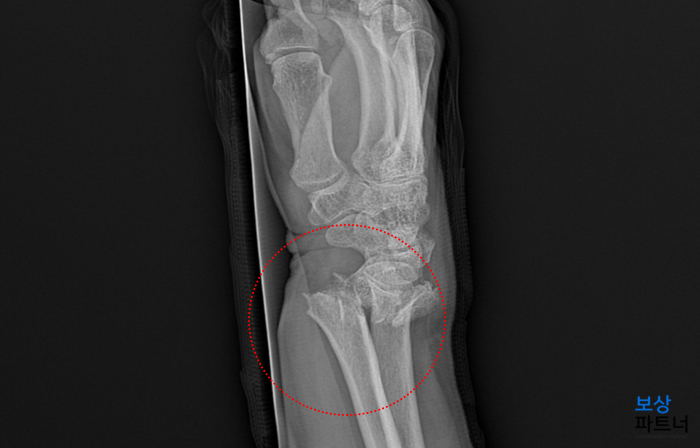

질병명 : 우측 요골 원위부 관절내 분쇄골절 및 척골 경상돌기 골절 (s5260) 우측 늑골의 염좌 (s2340) 진단 결과, 손목 부위의 뼈인 요골과 척골의 골절을 확인할 수 있었는데요. 관절을 이루고 있는 부근이 골절되었기 때문에 회복도 느리고 치료후에도 후유증이 남을 것을 예상되었습니다.

또한 골편이 여러 조각으로 나뉘는 분쇄골절의 양상을 띄었는데요. 이 역시 심한 골절상임을 알려주는 부분입니다. 즉시 수술적 치료가 필요하였으며, 관혈적 정복술 및 금속 내고정술 후에 깁스하여 안정을 취하게 되셨습니다.